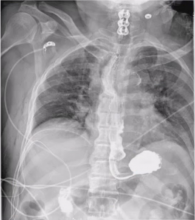

Technique: The patient was a 68-year-old gentleman with Parkinson's disease who had difficulty swallowing. A barium esophagogram and CT scan of the chest revealed a 4 cm epiphrenic esophageal diverticulum. Pre-operative EGD revealed the diverticulum arising at 32 cm from the incisors and the GE junction at 40 cm. The diverticulum, which contained retained food and tablets, was evacuated. Pulmonary function tests were adequate to perform a trans-thoracic operation. After intubation with a double lumen entrotracheal tube for lung isolation, EGD was performed on the table to empty the diverticulum of all its contents. An NGT was guided into the stomach. The patient was then repositioned in the left lateral decubitus position, prepped, and draped. The port placement is shown in the video. The diverticulum was mobilized and excised with a stapler, and the dehisced muscle was approximated. The esophageal hiatus was then dissected and the fat pad over the GE junction excised. The myotomy was performed and extended onto the stomach for 2 cm. A leak test was performed. The diaphragmatic hiatus was then approximated and the mediastinal pleura closed. Marcaine multilevel intercostal nerve block was performed. Blake drains were positioned in the chest.

The patient was extubated on the table. Post-operative management consisted of pain control. On the third postoperative day, an esophagogram was performed and no leak was detected. The NGT was discontinued and clear liquid diet started. The patient was discharged home on the fifth postoperative day.